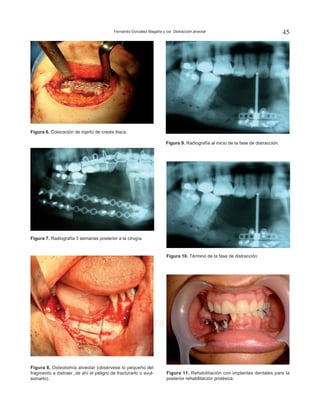

Figura 6. Colocación de injerto de cresta iliaca.

Figura 7. Radiografía 3 semanas posterior a la cirugía.

Figura 8. Osteotomía alveolar (obsérvese lo pequeño del

fragmento a distraer, de ahí el peligro de fracturarlo o avul-

sionarlo).

Figura 9. Radiografía al inicio de la fase de distracción.

Figura 10. Término de la fase de distracción.

Figura 11. Rehabilitación con implantes dentales para la

posterior rehabilitación protésica.

Una vez que se observa la integración del injerto

y la posterior resorción a nivel de la cresta alveolar

(Figura 7), se decide realizar bajo anestesia general el

retiro de material de osteosíntesis y la colocación de un

distractor alveolar subperióstico en el injerto (Figura 8).

Se lleva a cabo el protocolo de distracción (Figu-

ras 9 y 10) a razón de 1 mm por día y un periodo de

consolidación de ocho semanas.

A la paciente se le colocaron tres implantes den-

tales como fase quirúrgica final (Figura 11) para la

posterior colocación de una prótesis fija.